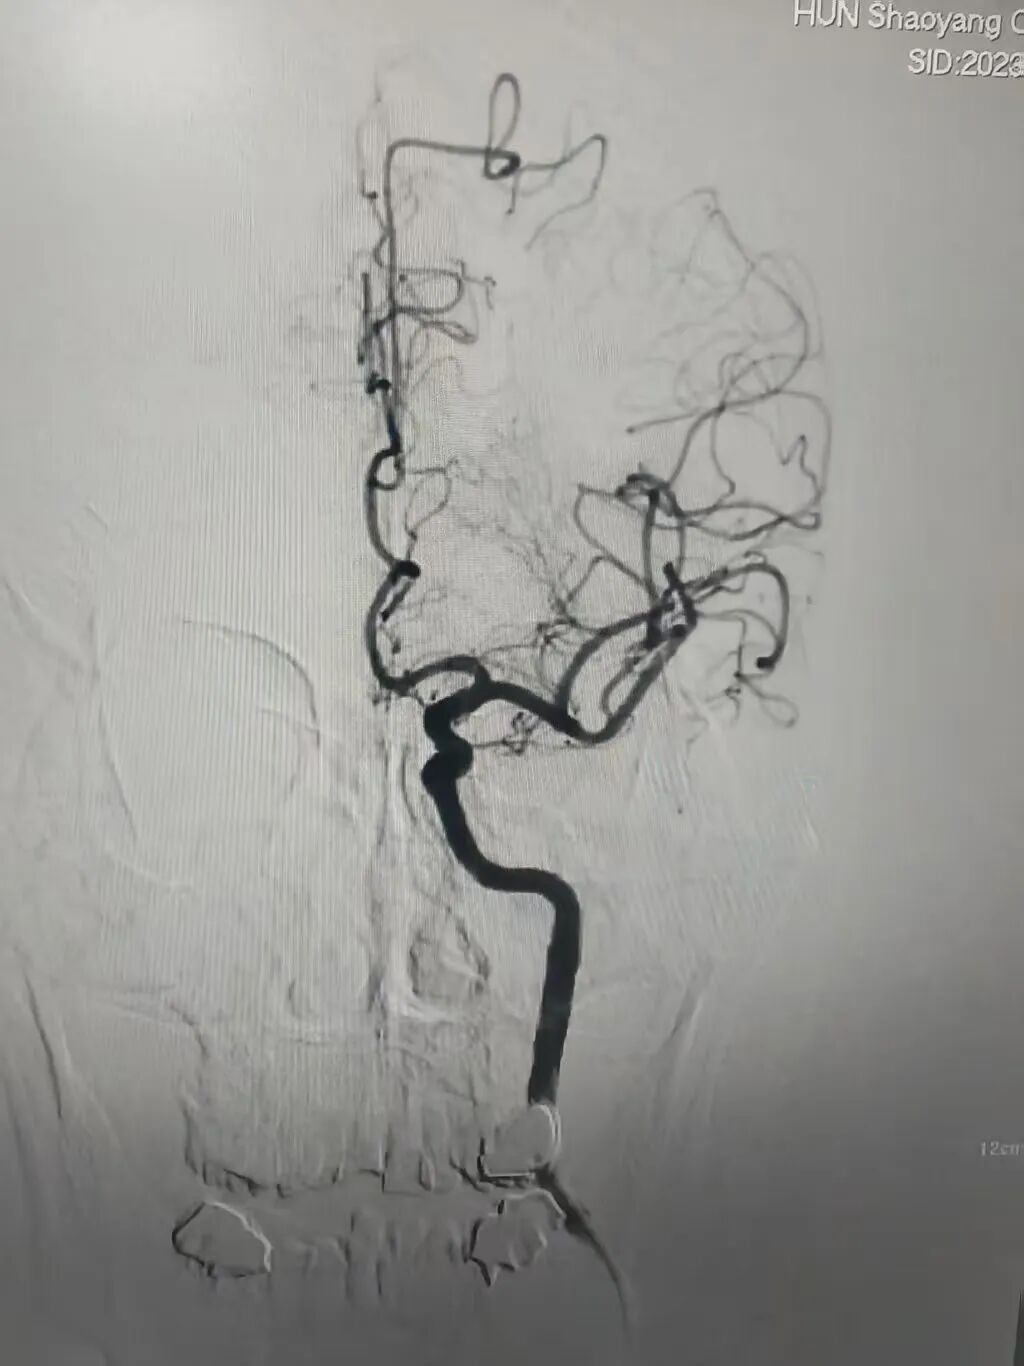

时间就是大脑!神经内科介入团队火速行动。19:50,患者被送入介入室,在局部麻醉下,邹永彪主任医师及其介入团队成员为患者立即施行了脑血管造影术,造影结果显示:左侧大脑中动脉闭塞,这是导致患者昏迷及右侧偏瘫的直接原因。团队凭借精湛技术,运用先进的取栓支架系统,精准定位并成功取出堵塞血管的暗红色血栓。术后造影显示,原先闭塞的左侧大脑中动脉及其分支恢复显影,前向血流重建!整个手术过程从穿刺到成功再通,仅用时约1小时。